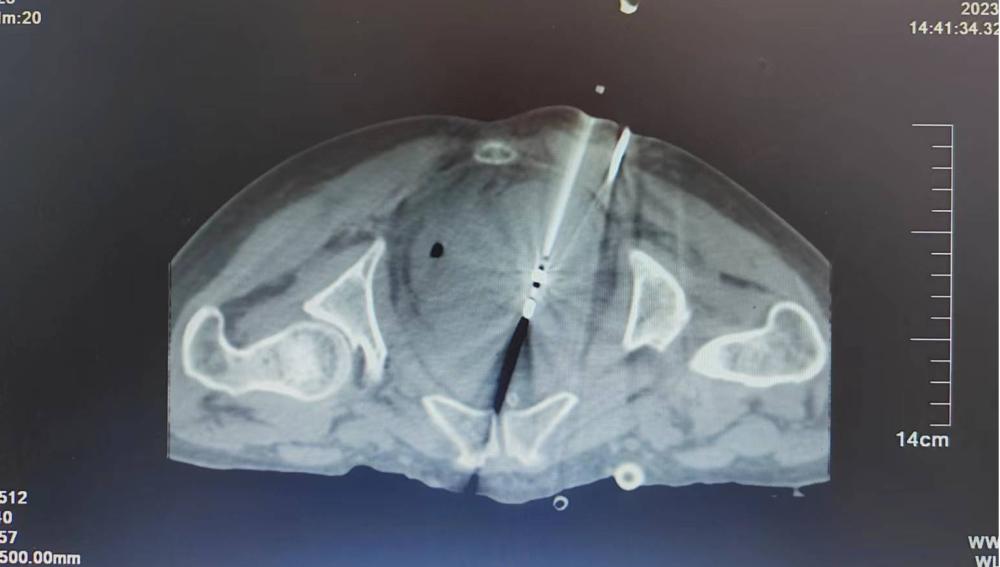

腹腔被巨大肿瘤填满是什么感觉?一名腹膜后脂肪肉瘤广泛转移的患者苦不堪言,由于腹膜肉瘤占据了大部分腹腔和几乎全部盆腔,不仅吃不进饭,排不出大小便,更痛苦的是腹部连同腰背的胀痛让人坐卧不宁,整夜无法入睡。肿瘤中心三科曹玉风主任团队采用微波消融技术将患者盆腔肿瘤缩小了60%,手术当晚患者腹部胀痛明显减轻安然入睡,术后第二天可以进食,生活质量的提高极大改善了患者的精神状态,为后续抗癌治疗创造了积极条件。